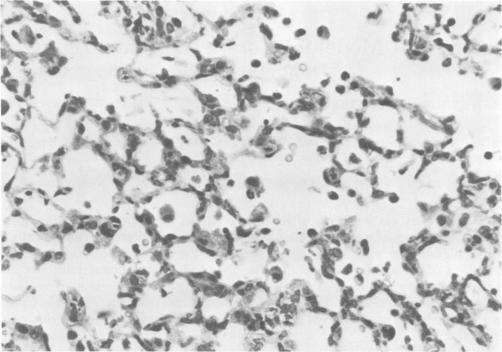

Sialodacryoadenitis virus (SDAV), a coronavirus of rats, evoked both serum neutralization and complement fixation antibody responses when inoculated intranasally in mice. Weanling gnotobiotic CD-1 mice inoculated intranasally with 10(3.0) mean tissue culture infective doses of SDAV remained asymptomatic. Virus was recovered from the nasopharynx, trachea, and lung from day 2 to day 7. Viral antigen was readily detected by indirect immunofluorescence in the lung but rarely in the nasopharynx. Infected mice developed interstitial pneumonia. Susceptible mice contact exposed to experimentally infected mice developed antibody to SDAV. Epizootiological studies indicated that retired breeder mice can have complement-fixing antibody to SDAV and mouse hepatitis virus (MHV) in the absence of MHV infection. These studies show that SDAV is infectious for mice and can be a pathogen for the respiratory system. Thus, SDAV infection of mice may be responsible for spurious seroconversions to MHV.

涎泪腺炎病毒(SDAV)是一种大鼠冠状病毒,经鼻内接种小鼠后可引发血清中和抗体及补体结合抗体反应。用10(3.0)平均组织培养感染剂量的SDAV经鼻内接种断奶无菌CD-1小鼠后,小鼠无症状。在第2天至第7天从鼻咽、气管和肺中可分离到病毒。通过间接免疫荧光法在肺中很容易检测到病毒抗原,但在鼻咽中很少检测到。受感染小鼠发生间质性肺炎。与实验感染小鼠接触的易感小鼠产生了针对SDAV的抗体。流行病学研究表明,种鼠在没有感染小鼠肝炎病毒(MHV)的情况下可能具有针对SDAV和MHV的补体结合抗体。这些研究表明,SDAV对小鼠具有传染性,可能是呼吸系统的病原体。因此,小鼠感染SDAV可能是导致假阳性MHV血清转化的原因。